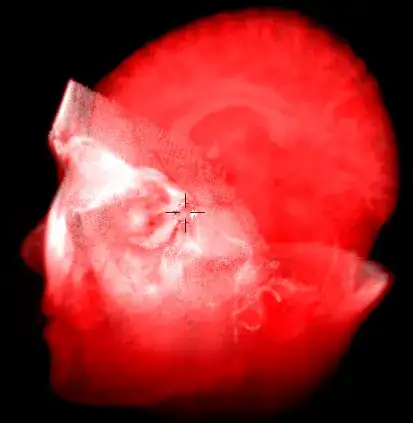

I know it's possible to do this in BI, but I need your help to do this in cycles.

For now, I have a setup to use an image sequence as volume but it only shows 1 slice/frame. I'm using generated texture coordinates for easy mapping (0-1 on each axis). The images are mapped on XY and I would like to use normalized frame# as Z coordinate to map the sequence as a volume.

Images sequence can be found here (I'm using 16-bit TIF files of MRBrain in this exemple).

Now, i played with it, and here's the result.

The "volume" object contains the volume shader (playing with the color ramp gives funny things) and the boolean modifiers (turn them off to see the complete volume, but reduce the final density multiplier for better view).

The "Slice Control" arrow empty controls the slice position/rotation.

The "Texture Mapping" object controls...the mapping, if it need some tunning (position, rotation, scale, and then tiling if necessary?).